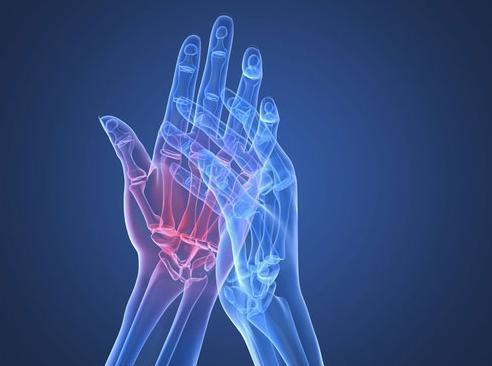

增生性骨关节病是指由于关节退行性变,以致关节软骨被破坏而引起的慢性关节病。又称退化性关节炎、骨关节炎及肥大性关节炎等。

起病缓慢,无全身症状,多为50岁以上的中老年。常为多关节发病,也有单关节发病者。受累关节可有持续性隐痛,活动增加时加重,休息后好转。疼痛常不严重,气压降低时加重,与气候变化有关。

有时可有急性疼痛发作,同时有关节僵硬感,偶尔可发现关节内有磨擦音。久坐后关节僵硬加重,稍活动后好转,有人称之为“休息痛”。后期关节肿胀、增大及运动受限,很少完全强直,一般表现为骨阻滞征。

典型症状

1.关节疼痛2.关节僵硬3.关节肿胀

4.骨干摩擦(音)5.关节无力、活动障碍